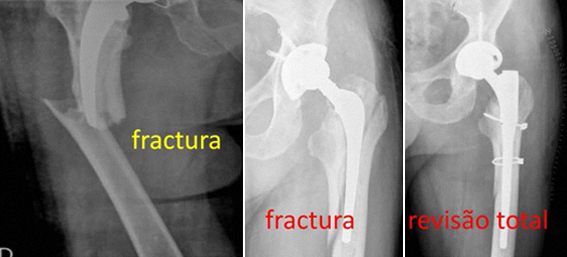

· FRACTURA PERIPROTÉSICA

Nos casos de fractura periprotésica, ou seja quando há fractura do fémur ao nível da haste femoral ou logo abaixo da extremidade da haste, a revisão é feita de acordo com as características da fractura.

Geralmente o Rx é suficiente para o diagnóstico.

O grau de dificuldade da revisão está mais relacionado com o tipo da fractura.